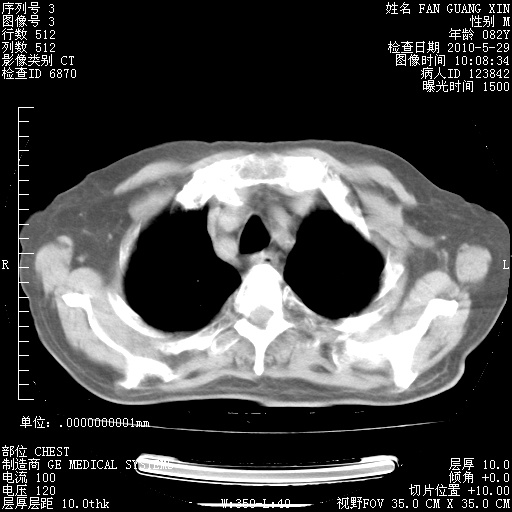

再治疗10天后的肺部CT

阅读此次胸部CT,肺间质渗出性改变较入院时有吸收。目前从体温、白细胞、中性分叶明显增高,肯定存在细菌感染(发生医院感染哦,若无消化道及泌尿系统等感染的依据,肺部感染可能大)。若你院头孢哌酮舒巴坦钠耐药率较高,同意你的方案,若48小时体温仍高,可考虑使用碳青霉稀类抗菌药物,同时可予超声雾化、注意滴数时加大液体量。白蛋白33.30g/L较低哦,需加强营养等支持治疗。